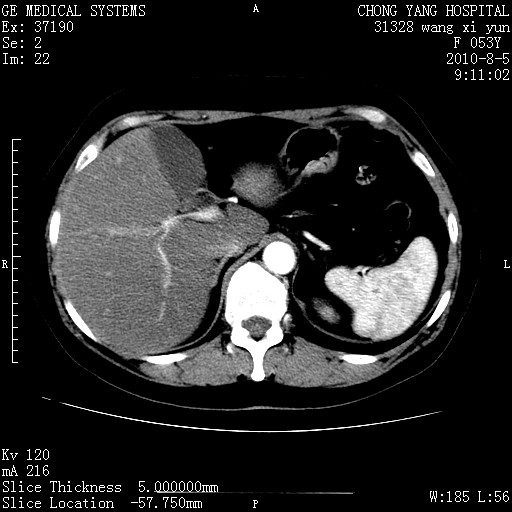

标题: CT28214:F41Y 血尿二十天,建议盆腔平扫加增强。

胆管细胞ca?

1)考虑肝左叶胆管细胞癌。2)脂肪肝。

支持胆管细胞ca。